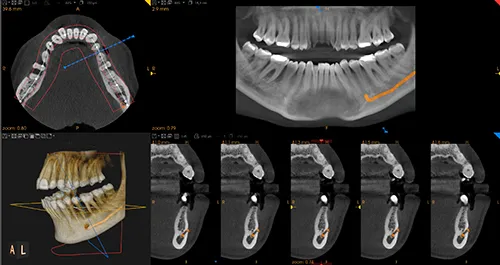

La TAC o Cone Beam 3D è una tecnica di imaging molto importante nella pianificazione di un trattamento di implantologia ed in particolare nelle tecniche di implantologia computer assistita.

È possibile, infatti, pianificare il posizionamento degli impianti con guide chirurgiche in casi con atrofie ossee (poco osso) o in prossimità di distretti anatomici importanti come il seno mascellare o il nervo alveolare inferiore senza rischi di alcun tipo.

L’utilizzo della TAC o Cone Beam 3D è utile anche in altri campi dell’odontoiatria come, per esempio, in endodonzia o in ortodonzia.